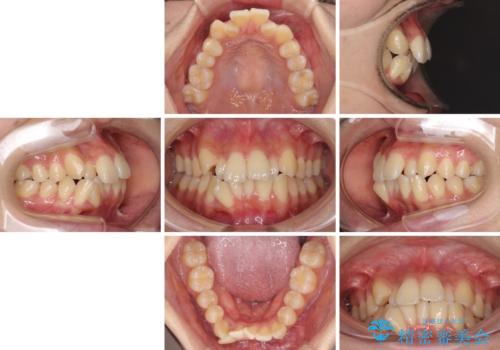

- 前歯のデコボコやクロスバイトと上顎の前突感による口の閉じにくさを気にして来院された患者様です。

目立たない装置を希望されたので、上顎が裏側装置のハーフリンガルを選択し、上下左右の小臼歯(計4歯)を抜歯して矯正治療を行うこととしました。

表側のワイヤー矯正に比べると治療期間は長く、費用も高額となりますが、どうしても目立たせたくないという方にはお勧めの抜歯矯正です。